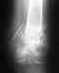

Надо разрабатывать движения. Местный остеопороз, обусловленный временным снижением нагрузок, после возврата к обычной двигательной активности постепенно самоликвидируется. Никаких медикаментов по этому поводу не нужно.